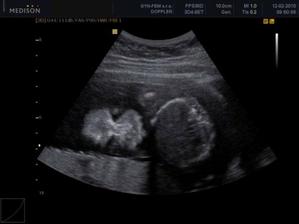

30.12. Jsem se byla zaregistrovat k porodu u Apolináře. ROK 2010 🙂 TO SE BUDOU DÍT VĚCI. 12.1. interní vyšetření + EKG a odběr - všechno OK, 14.1. UTZ žil kvůli natékání nohou (už ráno mám kotníky jako bambule). Výsledek: tromboza nehrozí UF!, nedomýkavost chlopní tepen, pže tělo je víc zatíženo. Doporučeno: nosit těhu punčochy, hodně pít, víc chodit, málo sedět a stát. Pak jsem utíkala na gyn na triplle testy a sestra mě objednala i na velký UTZ kam půjde i manža a budeme mimíska mít na DVD. Jsme oba natěšený! 20.1. UTZ ledvin - vše v pořádku. Tak velký UTZ proběhl OK. Nechceme vědět co to bude tak to stále nevíme 🙂)) . Triplletesty jsou taky v pořádku. 18.2. poradna - tak jsem měla nízký tlak 🙂)) jindy ho mám vysoký tak jsou trošku zmatený. Říkám, že mají blbý tlakoměr. Gynekologicky a miminkovsky všechno dobrý. 21.2. domluveno jméno pro klučíka - TOMÁŠEK .... ještě tu holčičku 😉)).